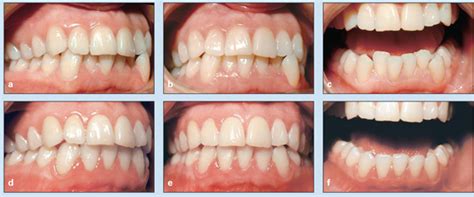

Hypodontia (Missing Teeth) People with hypodontia are born with missing teeth. Additionally, Hypodontia (congenitally missing teeth) can affect children's baby teeth and permanent teeth. Furthermore, This article delves into the causes, prevalence, clinical features, diagnostic approaches, and treatment options for hypodontia. Moreover, Hypodontia refers to the absence of one or more teeth. These findings regarding Hypodontia A Team Approach To Management provide comprehensive context for understanding this subject.

This article delves into the causes, prevalence, clinical features, diagnostic approaches, and treatment options for hypodontia

Apr 9, 2025 · What Is Hypodontia? Hypodontia is the most common dental anomaly that refers to the absence of 1 to 5 teeth. It results in the formation of gaps and spaces, which can result in the …